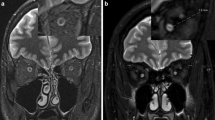

This study was performed in accordance with an approved Human Studies Protocol at the Washington University School of Medicine. The retrospective study covered a period of 8 years from 2005 to 2012, and included children with NF1 who underwent magnetic resonance imaging (MRI) (n = 29) as well as children without NF1 who underwent MRI for the evaluation of headaches (n = 18). The children were categorized into three groups: controls (n = 18), NF1 subjects without optic pathway glioma (n = 18) and NF1 subjects with optic pathway glioma (n = 11) (Fig. 1). The identification of optic pathway glioma was previously determined based on the interpreting radiologist’s opinion, typically due to thickening of the optic nerve/chiasm and/or associated gadolinium enhancement on MRI as an indication of glioma (Fig. 1). Similarly, although tortuosity has not been clearly defined, radiologists have previously noted several tortuous nerves in certain children with NF1, based on subjective assessments.

Based on the quantitative measurements of the tortuosity index, the mean optic nerve tortuosity indices in the control group for the right and left nerves were 14.9% (SD = 2.1) and 15.0% (SD = 2.2), respectively. Within the NF1 subjects, those without optic pathway gliomas had mean tortuosity indices of 26.9% (SD = 9.0) and 24.3% (SD = 4.3) for right and left optic nerves, respectively. In addition, NF1 patients with optic pathway gliomas had mean tortuosity indices of 27.0% (SD = 6.9) and 24.5% (SD = 6.2) for right and left optic nerves, respectively (Table 2). Post hoc analysis demonstrated that the controls had significantly lower tortuosity than NF1 subjects with optic pathway glioma (P < 0.001) and NF1 subjects without optic pathway glioma (P < 0.001), but the difference between the two NF1 groups was not significant (P = 0.979) (Fig. 4). Multivariate analysis showed that age (P = 0.173) and gender (P = 0.100) were not significantly associated with the quantitative tortuosity score, and the conclusion regarding between-group differences remained the same after adjusting for age and gender. The same conclusions were replicated in the analyses using retest scores (Table 2).

Optic nerve tortuosity indices measured by the quantitative scoring system, indicating higher tortuosity indices for NF1 subjects than for controls (P < 0.001). a Optic nerves of all the children in the study. Optic nerves previously noted as “tortuous” by radiologists are represented by an asterisk. b Right optic nerves only. c Left optic nerves only